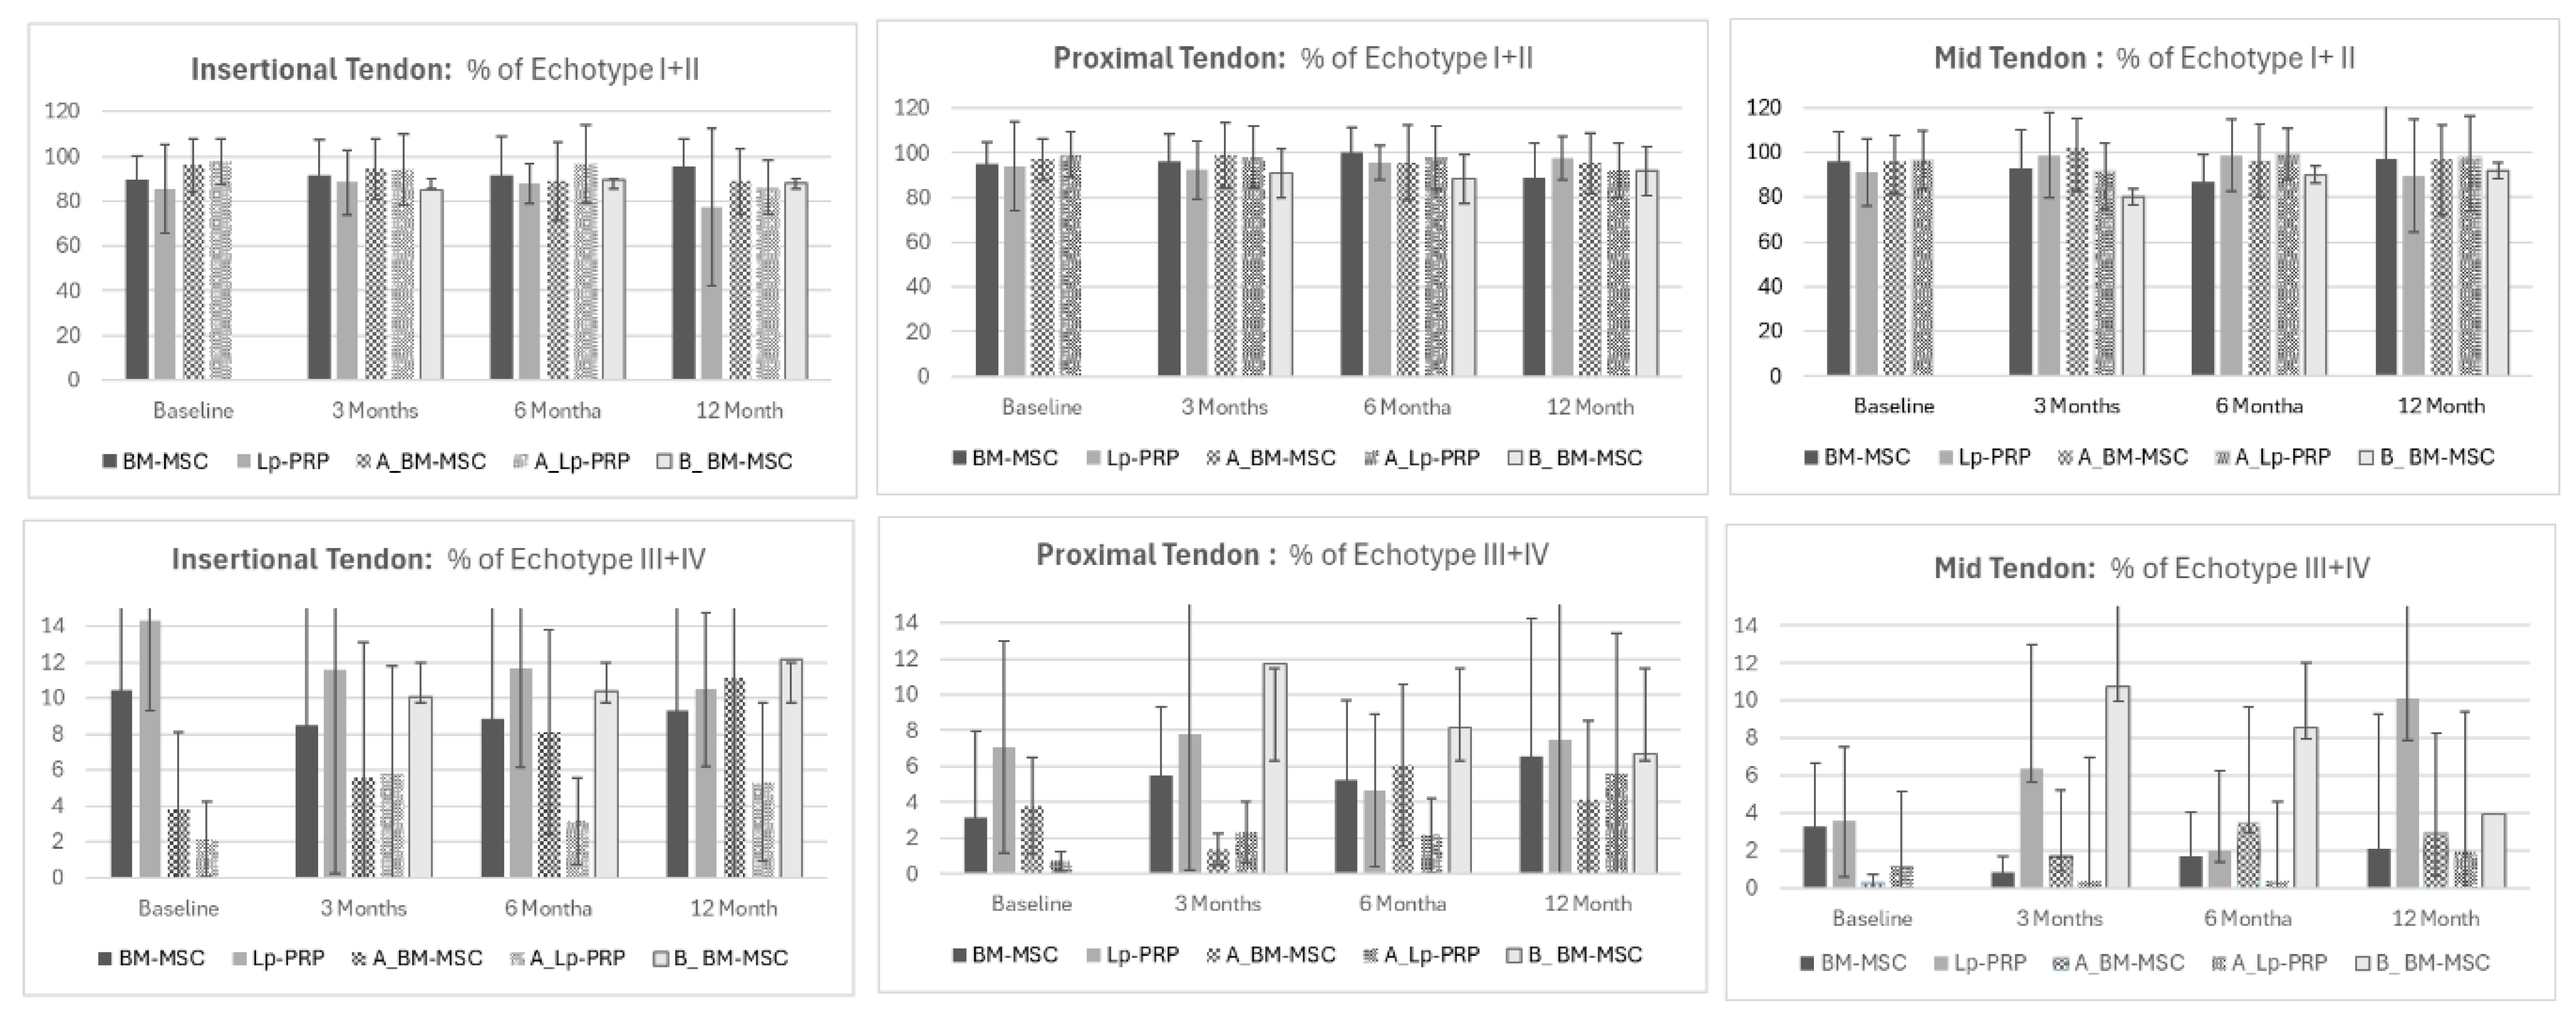

3.1. Evaluation of Echo-Types between BM-MSC and Lp-PRP

- Comparison between the differences in echo-types between BM-MSC and Lp-PRP showed higher disorganization in the Lp-PRP group after 3 months in echo-types II and III in the mid-tendon (echo-type II: BM-MSC 9.38 ± 14.81; MDC = 12.98; PRP −2.98 ± 8.4; MDC = 0.05; p = 0.04; ES = 1.06) (echo-type III: BM-MSC −0.65 ± 4.38; MDC = 4.85; PRP 9.61 ± 8.84; MDC = 0.29; p = 0.02; ES = −1.47).

- Similar results were seen after six months, with Lp-PRP still showing a higher disorganized tendon structure at echo-type III compared to BM-MSC (BM-MSC = −0.19 ± 2.01; MDC = 2.23; Lp-PRP 4.65 ± 5.17; MDC = 0.17; p = 0.03; ES = −1.4).

- Our results demonstrate that BM-MSC shows greater improvement in tendon organization than Lp-PRP at 3 and 6 months.

3.2. Evaluation of Echo-Types between BM-MSC and B-BM-MSC

- Comparisons of patellar tendon structure between BM-MSC as the first treatment and B-BM-MSC as the second biological treatment showed that BM-MSC presented more organized tendon structures at the proximal tendon for echo-type I after 6 months compared to B-BM-MSC (BM-MSC = 1.13 ± 12.6; MDC = 6.05; B-BM-MSC = −8.83 ± 20.46; MDC = 9.82; p = 0.04; ES = 0.58).

- Interestingly, long-term results showed more organized tendon fibers in the B-BM-MSC group compared to the first BM-MSC treatment for echo-types III and IV at the insertional tendon (echo-type III: BM-MSC = −1.67 ± 2.85; MDC = 2.62; B-BM-MSC 2.15 ± 6.18; MDC = 5.68; p = 0.04; ES = −0.79) (echo-type IV: BM-MSC = −0.89 ± 1.75; MDC = 2.02; B-BM-MSC 1.22 ± 3.32; MDC = 3.91; p = 0.04; ES = −0.79).

3.4. Evaluation of Echo-Type between Symptomatic and Asymptomatic

- Patellar tendon structural changes between symptomatic and asymptomatic tendons showed minor significant differences. Only the mid-tendon showed significant differences for echo-type I in the BM-MSC group after 3 months. BM-MSC showed a higher amount of organized tendon fibers (6.92% ± 22.77) compared to A-BM-MSC (−2.35 ± 7.93; p = 0.02; ES = 0.1). Additionally, the MDC was 10.93% for BM-MSC and 3.8% for A-BM-MSC, with a large effect size of 0.1.

- The results confirm the positive effect of the treated tendon with BM-MSC compared to the untreated tendon. Conversely, Lp-PRP treatment did not show enough tendon structural change as the comparison between Lp-PRP and the asymptomatic Lp-PRP contralateral tendon showed no significant differences.